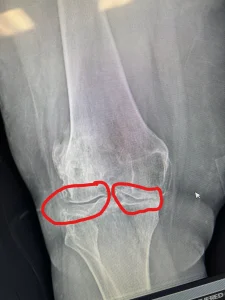

These are before/after X-rays of a patient’s right knee after getting stem cell therapy at Stem Cell Carolina. The “before” X-ray was taken in April 2021 before this patient had adipose-derived stem cells with PRP. The X-ray with red circles shows where there is an increase in joint space if you compare it to the “before” X-rays.